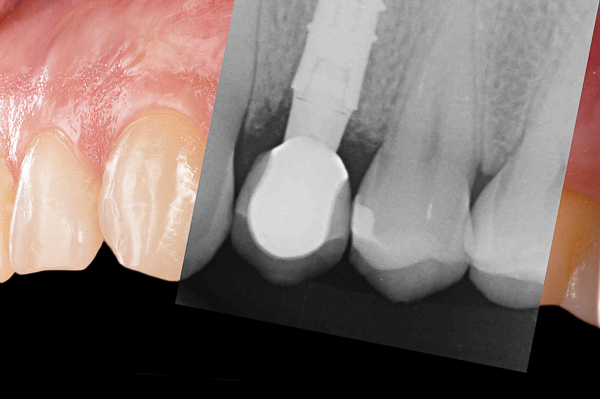

A seguito dell'analisi radiografica viene pianificata l'estrazione atraumatica del premolare con l'inserimento contestuale di un impianto Shelta. La riabilitazione immediata viene eseguita con un pilastro XA per protesi avvitata, su cui viene fissato un provvisorio realizzato in laboratorio secondo i principi dei profili di emergenza della tecnica B.O.P.T.

Donna, 37 anni, non fumatrice, con una buona igiene, si presenta in studio con un fallimento del trattamento endodontico dell'elemento 1.4.